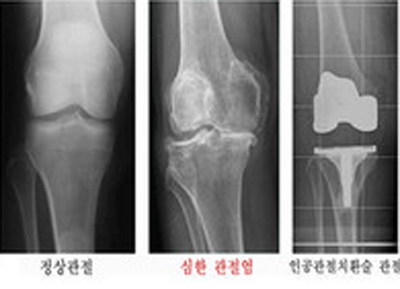

관절염 중 퇴행성 관절염은 관절면을 이루고 있는 연골이 닳아 없어져서 뼈끼리 맞닿아 마찰이 돼 통증, 부종, 관절 운동 장애 등을 일으키는 질환이다. 치료로는 질환의 진행 단계에 따라 비약물적 치료, 약물 치료, 수술 등을 적용 할 수 있지만, 증상이 심한 퇴행성 관절염에는 증상을 경감시키기 위한 비수술적 치료만으로는 만족스러운 결과를 얻기 어렵다. 퇴행성 관절염은 손상된 골 표면을 절제하고 마찰이 적은 인공 관절 기구로 대체하여 삽입하는 인공 관절 수술이 매우 효과적인 방법이다.

서울스카이병원 정형외과 원장 유재호 박사는 “방사선 사진 상의 관절염 진행 정도와 환자가 직접 느끼는 동통을 포함한 관절염 증상은 꼭 일치하는 것은 아니다. 어떤 사람은 관절염 자체는 심하게 진행된 상태이지만 증상이 심하지 않은 경우도 있고 또 어떤 사람은 관절염의 진행 정도에 비하여 심한 증상을 호소하기도 한다. 인공관절 수술은 방사선 사진 상에서 진행된 관절염이 확인되는 증상이 심한 환자에서 적용할 수 있다”고 전했다.